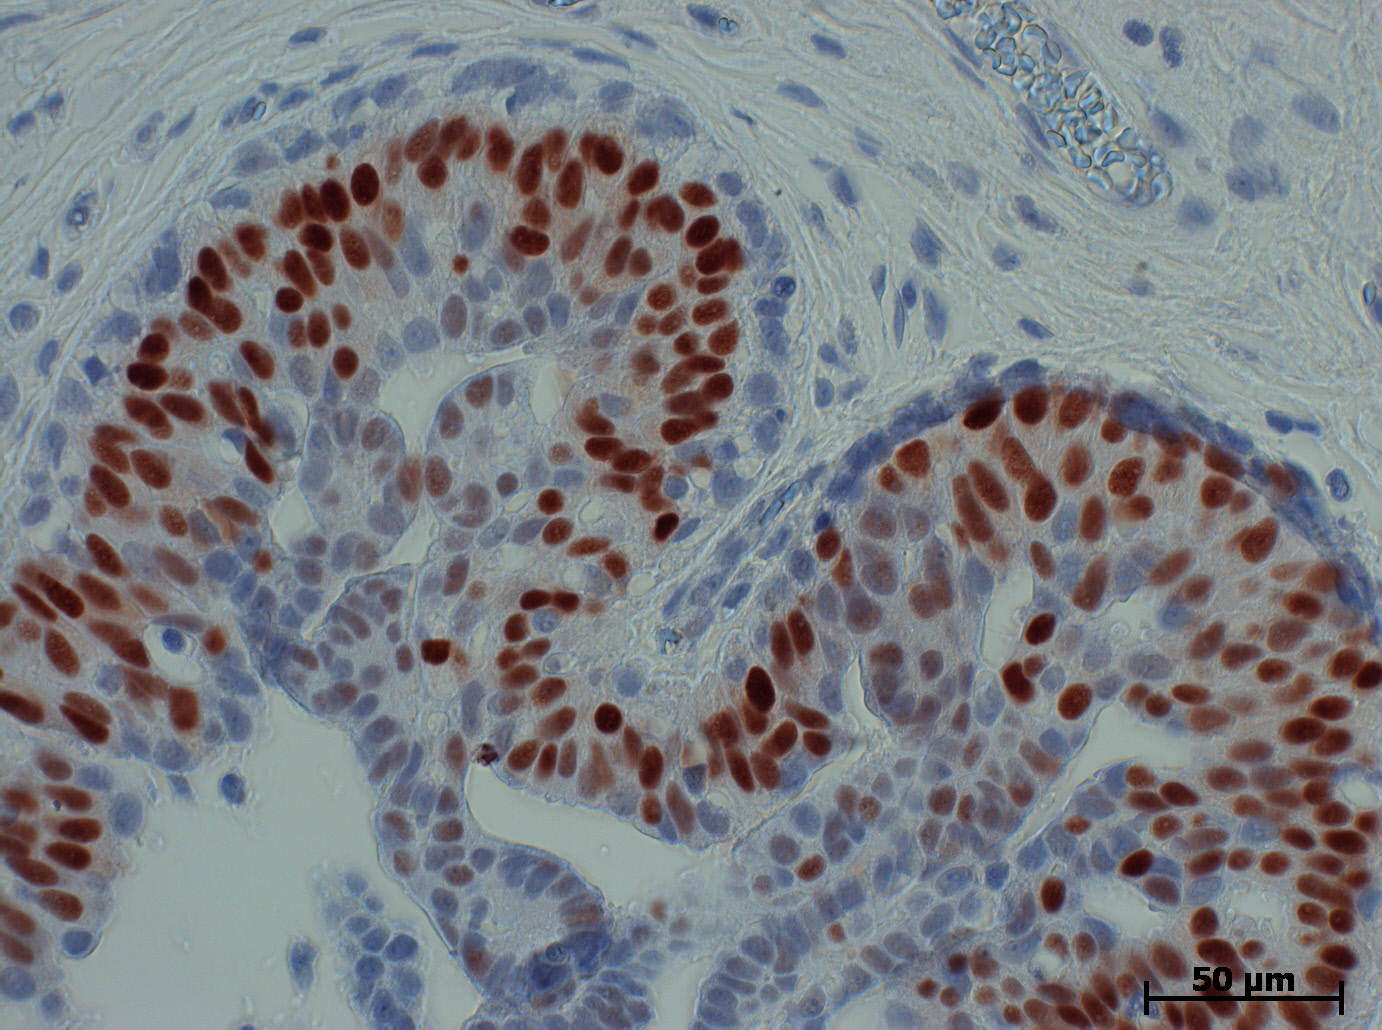

AmpliStain OPEN™ - novel detection systems for ImmunoHistoChemistry (IHC) and Colorimetric In-Situ Hybridization (CISH) - from the original developer and sole manufacturer of the PolyHRP Conjugates Launched in 1990, PolyHRP predated dextran and other backbone polymeric conjugates. However, PolyHRP was developed primarily for UltraSensitive ELISA and is not applicable in IHC staining protocols as it can not permeate into tissue sections because of its larger size. With PolyHRP as such SDT has regretfully been longer time inactive in addressing IHC marketplace needs. While belatedly, now we offer a comprehensive line of the enhanced detection products for the most demanding IHC applications. We are sure that a long way made by AmpliStain™ and StrongZyme™ in reaching IHC customers will be paid off by the excellent high quality performance of our products along with their well recognized consistency, stability and robustness. We offer products for 1-Step immunostaining (read more) OPEN™ stands not only for Oligo-Polymer Enhancement, but also has a direct meaning. Taking into consideration diversity of routine clinical diagnostic and experimental research IHC applications along with very different customer work traditions we supply all AmpliStain™ reagents with no fixed use instructions. AmpliStain™ is an open system suggesting unrestricted variety of tailored custom protocols optimized by ImmunoHistoChemists addressing their specific needs. All AmpliStain™ reagents supplied in Ready to Use RESERVE™ format, i.e. at maximum working strength for High Sensitivity detection of the most challenging - rare, low-abundance and/or hidden antigens using fast 10-15-min. incubation protocols - also with weak, low affinity primary antibodies. With many regular, well accessible / abundant antigens and/or within longer incubation protocols AmpliStain™ reagents can be diluted to the smaller working strength concentrations that will still ensure highly sensitive detection. For that reason, along with AmpliStain™ reagents, we offer Universal IHC Diluent/Blocker/Stabilizer (#UDBS, a separately available item) as a complementary support product that can be used for diluting of all StrongZyme™ conjugates and, if wanted, primary antibodies. UDBS description Useful links and relevant publications: Signal amplification in immunohistochemistry: Loose-jointed deformable heteropolymeric HRP conjugates vs. linear polymer backbone HRP conjugates by Igor Buchwalow et al. in Acta Histochemica Volume 115, Issue 6, July 2013, Pages 587–594 http://www.sciencedirect.com/science/article/pii/S0065128112001833 http://dx.doi.org/10.1016/j.acthis.2012.12.008 |

![]() ![]() ![]() click here for more images |